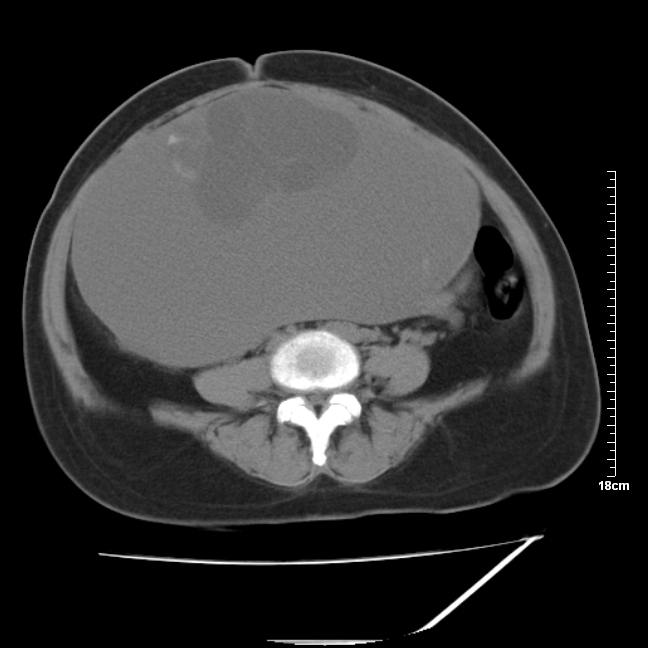

以下是引用jinning在2007-5-17 11:18:00的发言:[br]考虑右侧卵巢囊腺瘤合并少量出血可能性大